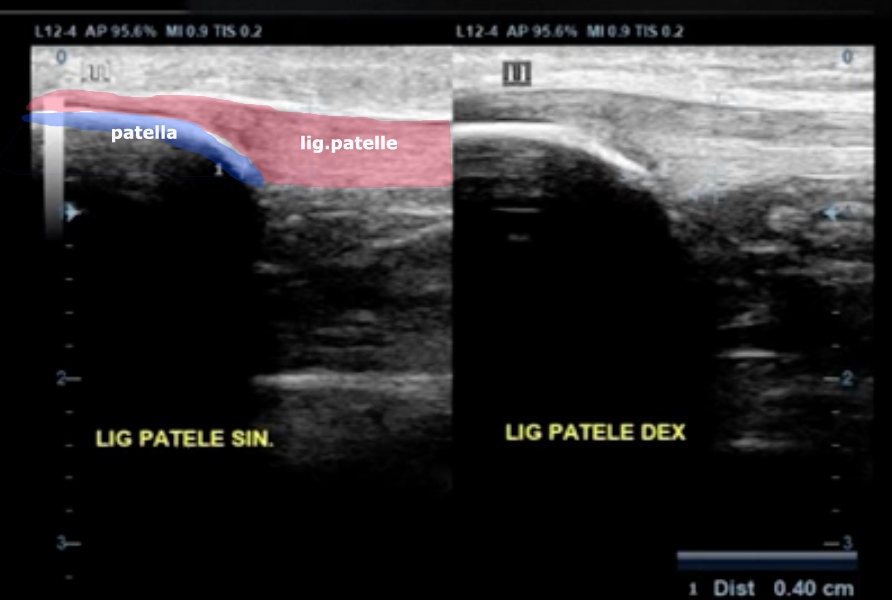

Jumper's knee MSK Ultrasound Physiotherapy News Jumper's Knee Test Triple hop test and vertical jump are great tests to measure suitability for return to training. A positive clarke’s test can help a healthcare provider tell whether knee pain is caused by cartilage breakdown: Contrary to traditional belief, a jumper's knee does not involve inflammation of the knee extensor tendons. Jumper’s knee is inflammation of your patellar tendon, the tendon. Jumper's Knee Test.